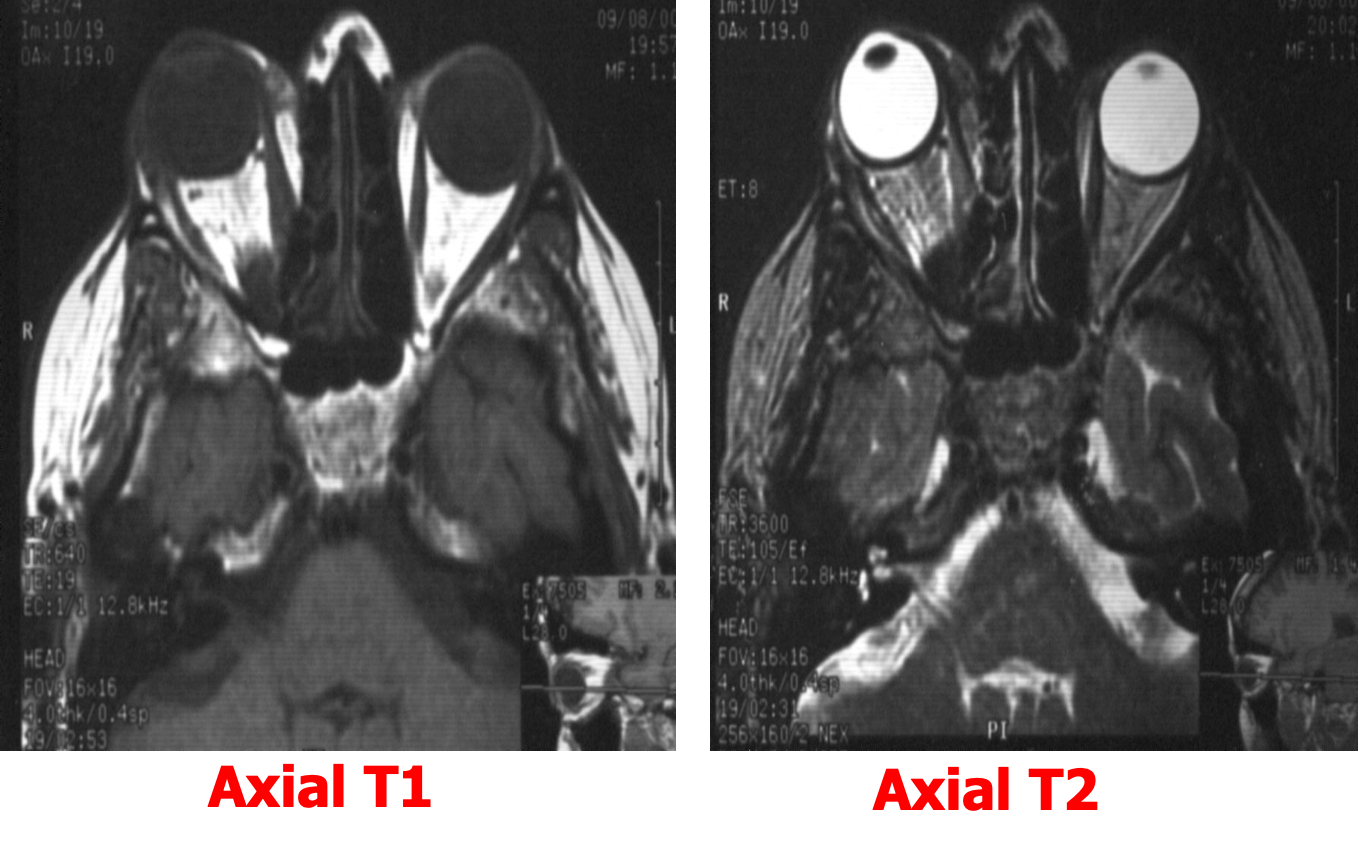

Multiplanar imaging: Axial ,Sagittal & Coronal Any MR examination should include T1 and T2 Weighted images

T1 WIs [CSF BLACK ] T2 WIs [CSF BRIGHT ]